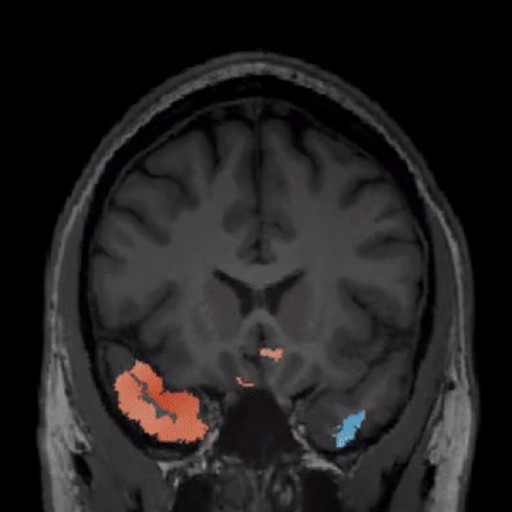

Diagnostics. AI-powered lesion identification combined with expert radiologist validation delivers comprehensive case reports

BrainScores was built specifically for epilepsy surgery. Generic neuroimaging platforms serve multiple conditions but lack the depth required for focal cortical dysplasia detection

BrainScores was built exclusively for epilepsy surgery. Generic neuroimaging platforms serve multiple conditions but lack the depth required for focal cortical dysplasia detection.